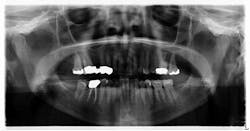

A healthy 74-year-old female presents for a comprehensive exam. A panoramic radiograph is taken. A radiopaque mass measuring approximately 0.5 x 0.5 inches is noted on the left side, just anterior to the angle of the mandible (figure 1). The area is asymptomatic upon palpation. The patient reports no knowledge of the lesion. Access to a previous pan from six years prior is acquired. The same lesion is noted on the radiograph, albeit somewhat less distinctive (figure 2).